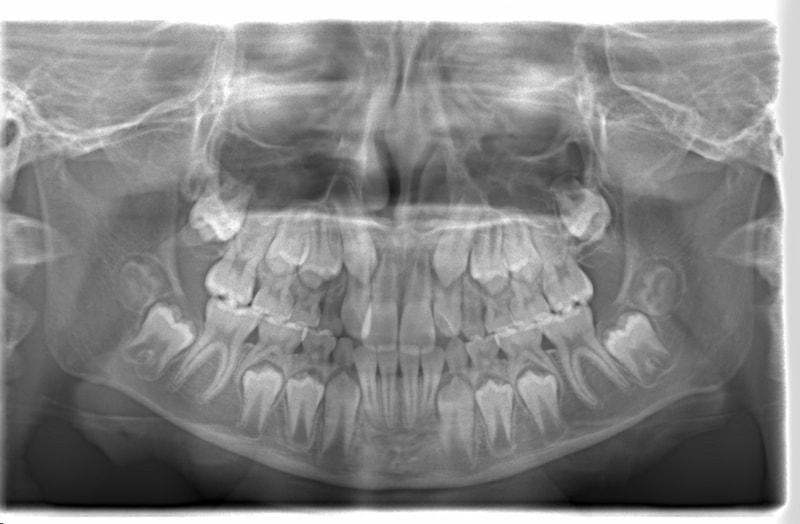

FX(フェイシャルアキシス)は85度なので東洋人の平均値に近く、下顎が前方に過剰成長するリスクは強くはありません。

しかしやはり上顎は劣成長で、下顎が優位な状態ではあります。

上下顎のギャップはありますが、顔面自体の幅径は良好な値を示していますので、スペース不足は拡大することによって解決できポテンシャルはあると考えられます。

左右の非対称もさほど強くありません。

骨年齢は実年齢よりも低めなので、今後下顎の旺盛な成長が見込まれます。

検査時のレントゲン分析では、上下顎の関係は、上顎の劣成長があり下顎前突傾向という値がでておりましたが、前歯ジャンプ後はフェイスマスクの効果もあり、上下顎の関係は正常化しています。

上顎が若干優位になっていますので、今後の下顎の成長のための貯金になっているくらいです。